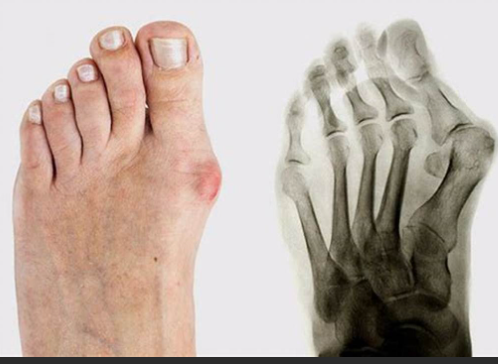

발가락 진단 및 의료 평가

언제 병원을 찾아야 할까?

만성적이거나 심한 발가락 통증을 경험한다면 의료 전문가와 상담하는 것이 중요합니다. 조기 진단과 치료는 추가 합병증을 방지하는 데 도움이 됩니다.

진단 검사

발가락 통증의 원인을 파악하기 위해 의료 전문가는 X-선, 초음파 또는 MRI 검사를 포함한 다양한 진단 검사를 수행할 수 있습니다.